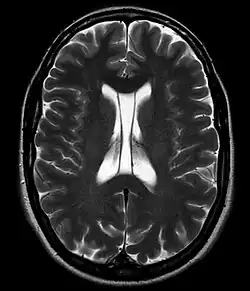

Jama przegrody przezroczystej (łac. cavum septi pellucidi, ang. cavum septum pellucidum) – często spotykany wariant anatomiczny budowy mózgowia, polegający na obecności wąskiej przestrzeni płynowej między dwiema blaszkami przegrody przezroczystej.